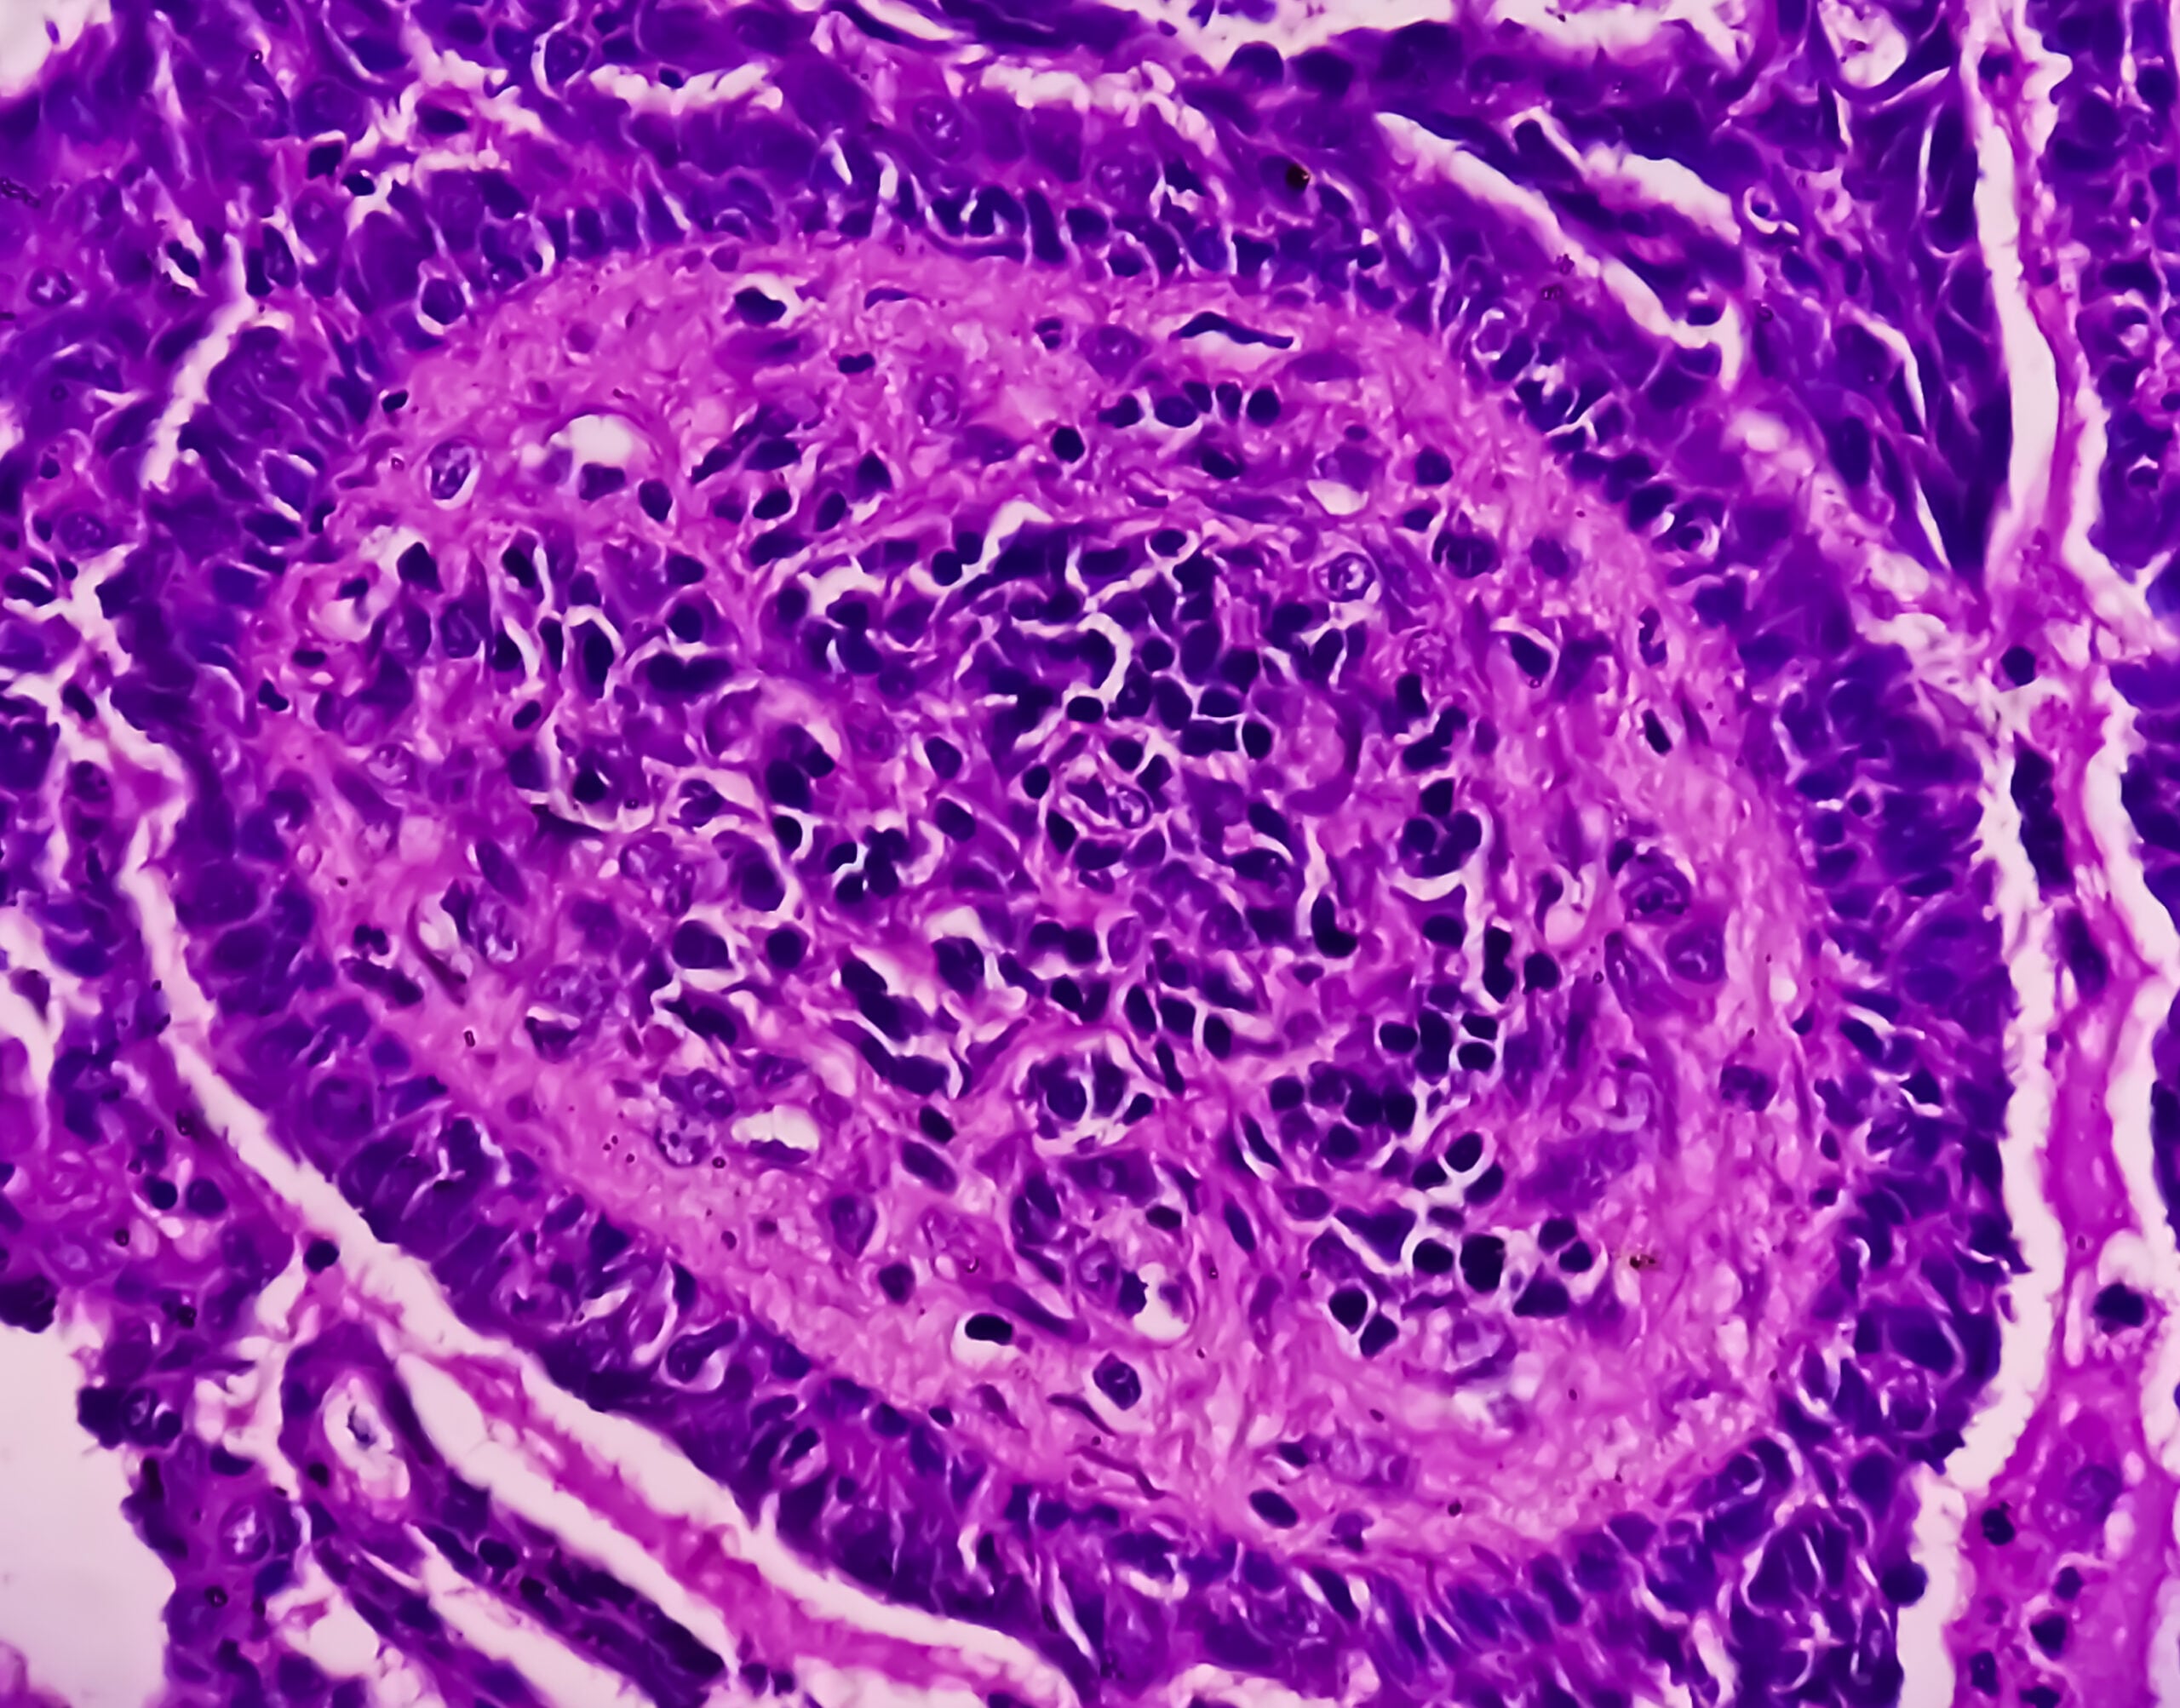

Multilocular cystic renal cell carcinoma (MCRCC)